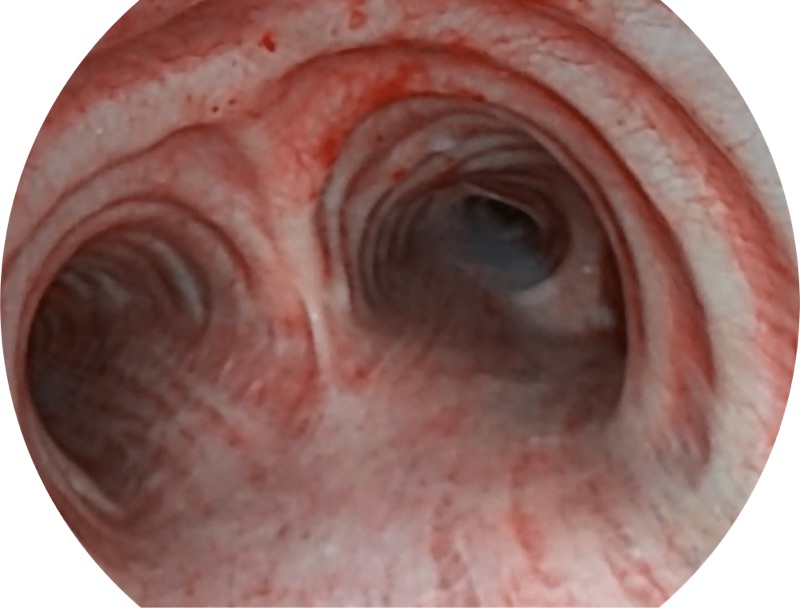

帮助医生更加清晰地观察气管表面病灶

EB-5H20具有4.9mm外径及2.0mm钳道提升对外围支气管检查能力